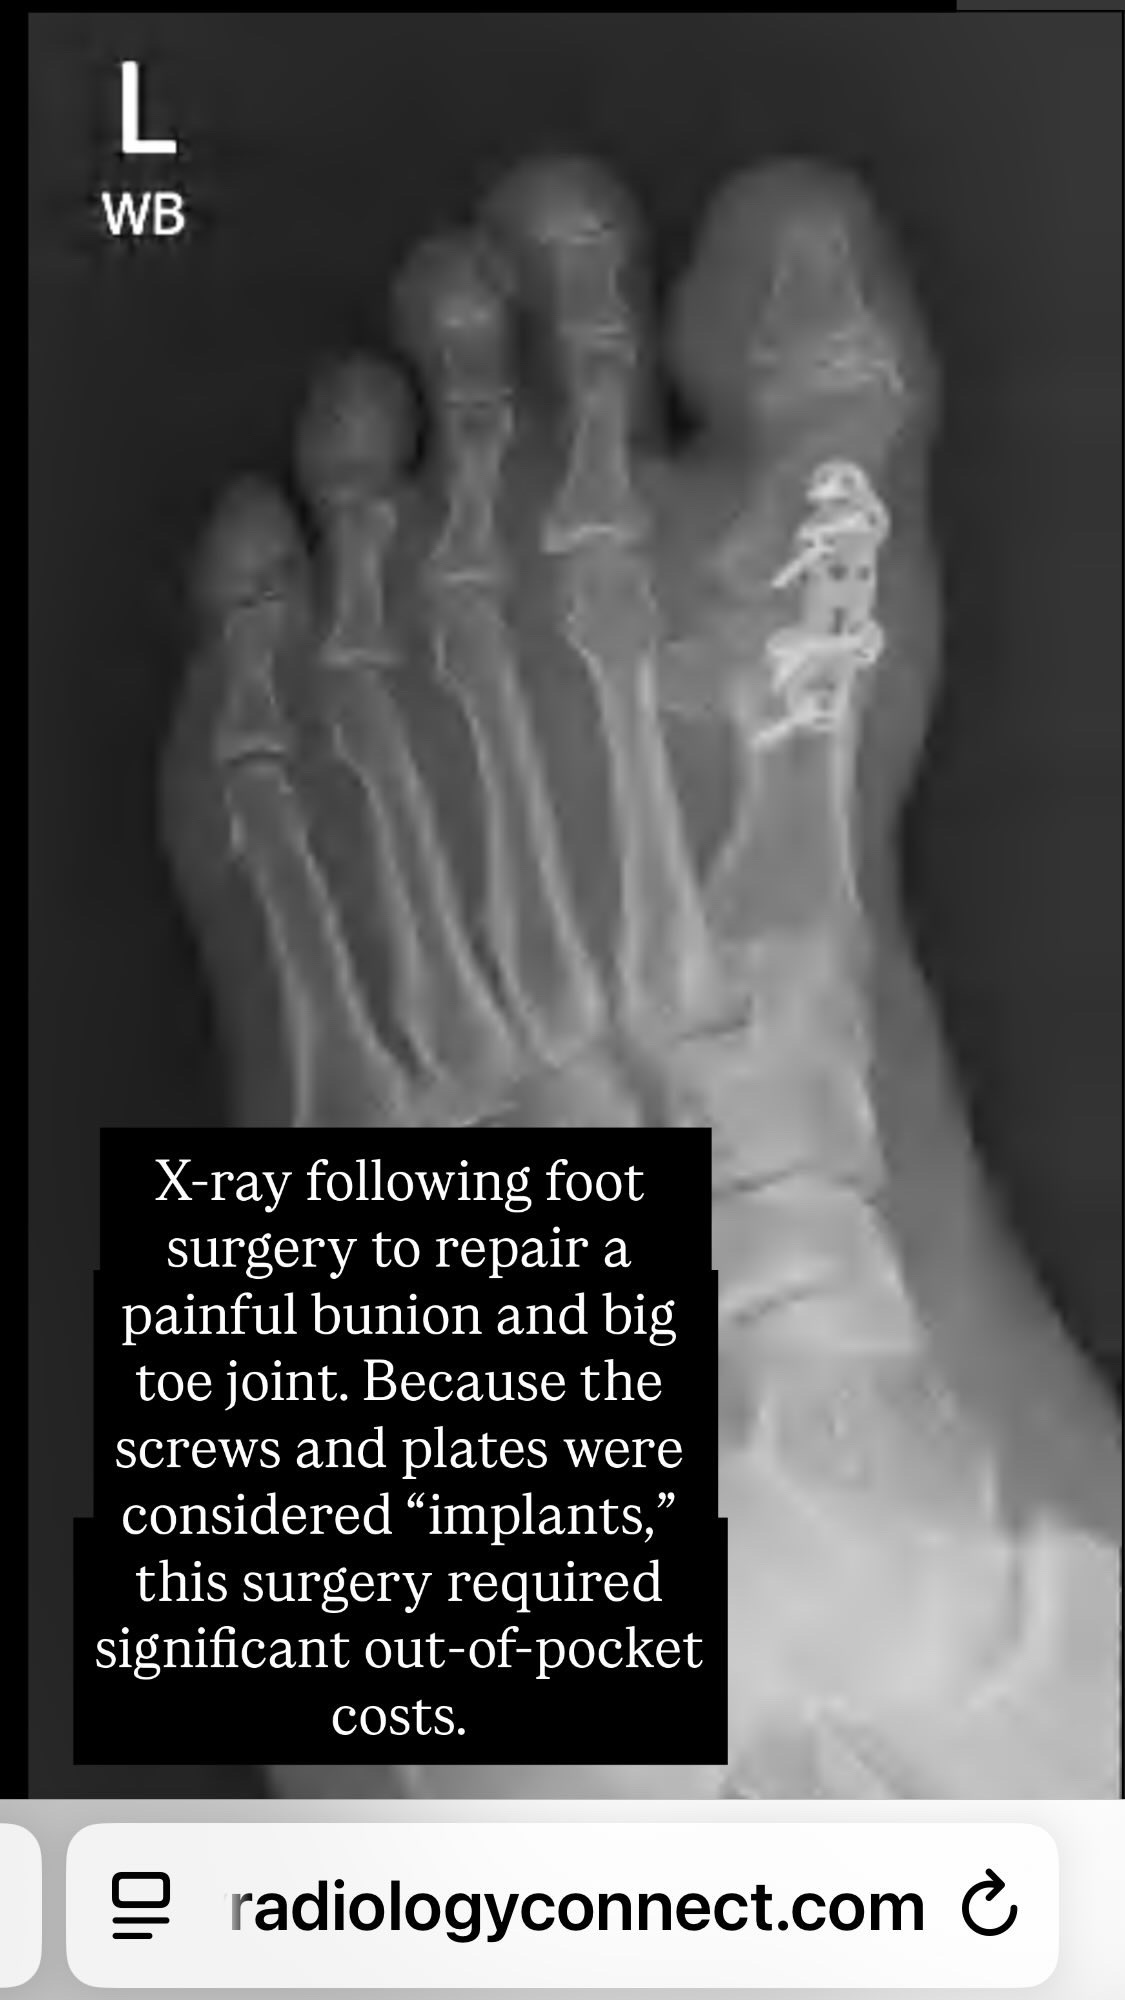

Earlier this year, I lost vision in one eye from a retinal vein occlusion, requiring several injections and laser surgeries. Shortly after, I was diagnosed with atrial fibrillation, wore a heart monitor, took blood thinners, and underwent heart ablation surgery. Years of dancing on Broadway and off-Broadway left my foot in terrible shape. Surgery was necessary, but insurance refused to cover the plates and screws, leaving me with significant out-of-pocket costs. Recovery is slow and painful, but I keep going because I have no other choice.